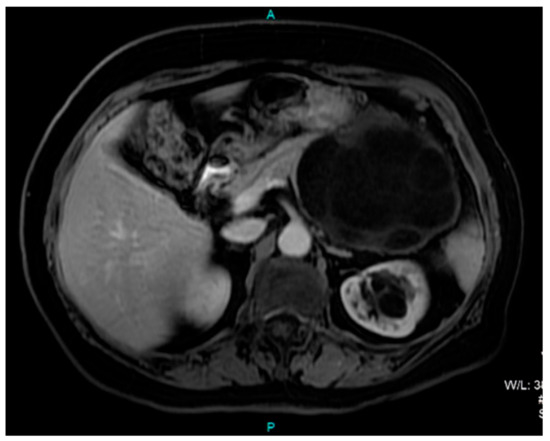

Pancreatic Hydatid Cyst Misdiagnosed as Mucinous Cystadenoma: CT and MRI Findings

2. Case Report